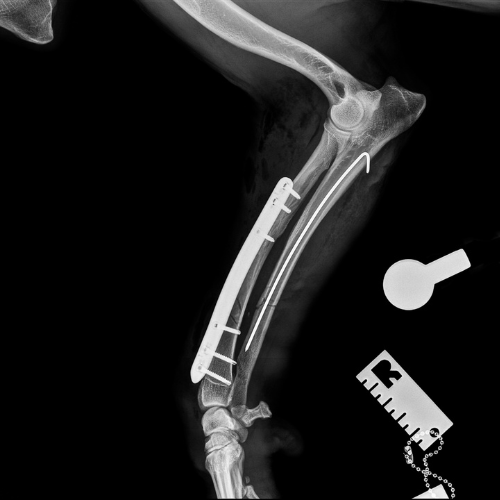

El servicio de traumatología está dirigido por Enrique Senís, especialista en traumatología y ortopedia por la Universidad Complutense de Madrid . Estamos orientados al diagnóstico y tratamiento de patologías del sistema musculoesquelético, incluyendo fracturas, luxaciones, rotura de ligamento cruzado y demás alteraciones articulares y deformidades óseas.

Disponemos de medios diagnósticos avanzados y aplicamos técnicas quirúrgicas de última generación en osteosíntesis, estabilización articular y corrección de deformidades, con el objetivo de restaurar la funcionalidad y minimizar el dolor en nuestros pacientes.